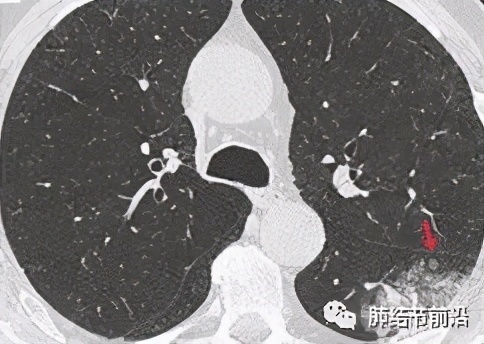

STAS的CT特点:这是重点!STAS 是一个术后的病理诊断,术前能否通过CT判断STAS的风险,可以对手术的时机和手术方式做最佳判断。如有STAS可能,则因尽早手术,并且需要做肺叶切除。 然而仅有少数情况下CT可以直接观察到,具体表现为:在主病灶周围显示不连续的转移灶。

大片混杂磨玻璃影,CT显示卫星灶,离主病灶10mm之内,为STAS